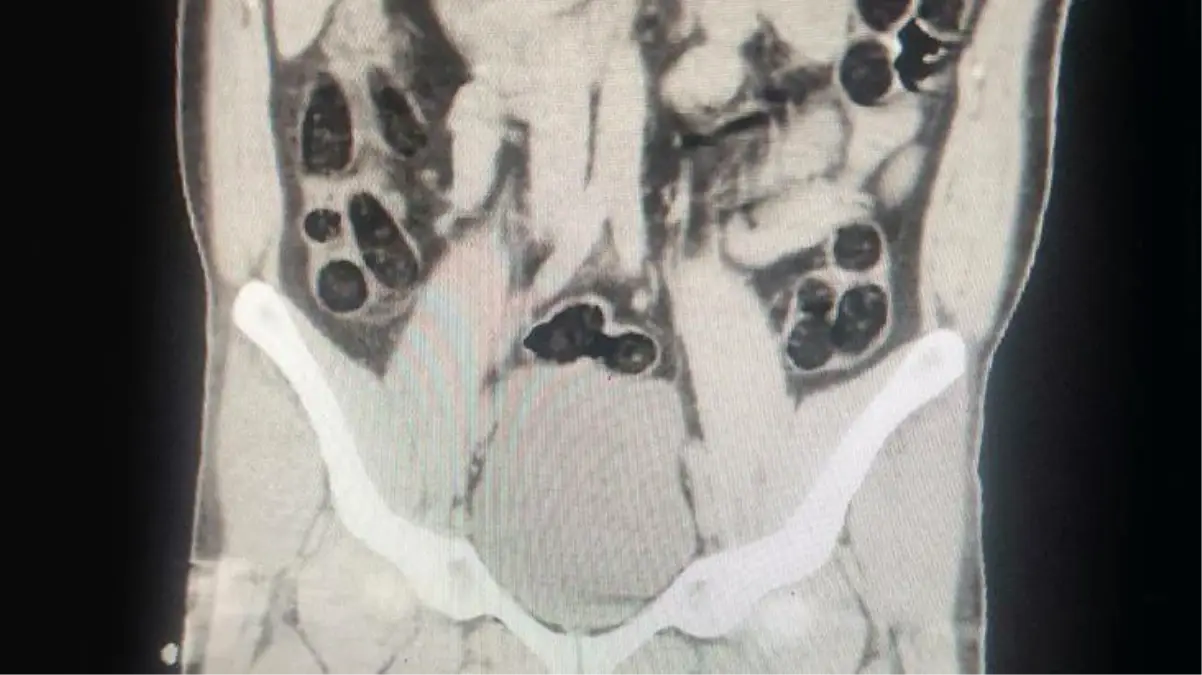

Operasyonda; otobüs ile seyahat eden 2 İran uyruklu şahsın yapılan kontrollerinde ve iç beden muayenesi sonucunda, şahıslardan birinin midesinde 76 paket halinde 714 gram uyuşturucu madde ele geçirildi.